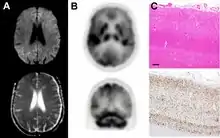

dwMRI, FDG PET and post mortem histology from a patient who presented with sCJD aged 66

• Focal or diffuse diffusion-restriction involving the cerebral cortex and/or basal ganglia. In about 24% of cases DWI shows only cortical hyperintensity; in 68%, cortical and subcortical abnormalities; and in 5%, only subcortical anomalies.[47] The most iconic and striking cortical abnormality has been called "cortical ribboning" or "cortical ribbon sign" due to hyperintensities resembling ribbons appearing in the cortex on MRI.[48] The involvement of the thalamus can be found in sCJD, is even stronger and constant in vCJD.[49]

• Varying degree of symmetric T2 hyperintense signal changes in the basal ganglia (i.e., caudate and putamen), and to a lesser extent globus pallidus and occipital cortex.[44]

Brain FDG PET-CT tends to be markedly abnormal, and is increasingly used in the investigation of dementias.

• Patients with CJD will normally have hypometabolism on FDG PET.[50]

Histopathology

Spongiform change in CJD

Testing of tissue remains the most definitive way of confirming the diagnosis of CJD, although it must be recognized that even biopsy is not always conclusive.[51]

In one-third of people with sporadic CJD, deposits of "prion protein (scrapie)", PrPSc, can be found in the skeletal muscle and/or the spleen.[52] Diagnosis of vCJD can be supported by biopsy of the tonsils, which harbor significant amounts of PrPSc; however, biopsy of brain tissue is the definitive diagnostic test for all other forms of prion disease. Due to its invasiveness, biopsy will not be done if clinical suspicion is sufficiently high or low. A negative biopsy does not rule out CJD, since it may predominate in a specific part of the brain.[53]

The classic histologic appearance is spongiform change in the gray matter: the presence of many round vacuoles from one to 50 micrometers in the neuropil, in all six cortical layers in the cerebral cortex or with diffuse involvement of the cerebellar molecular layer.[54] These vacuoles appear glassy or eosinophilic and may coalesce. Neuronal loss and gliosis are also seen.[55] Plaques of amyloid-like material can be seen in the neocortex in some cases of CJD.[56]